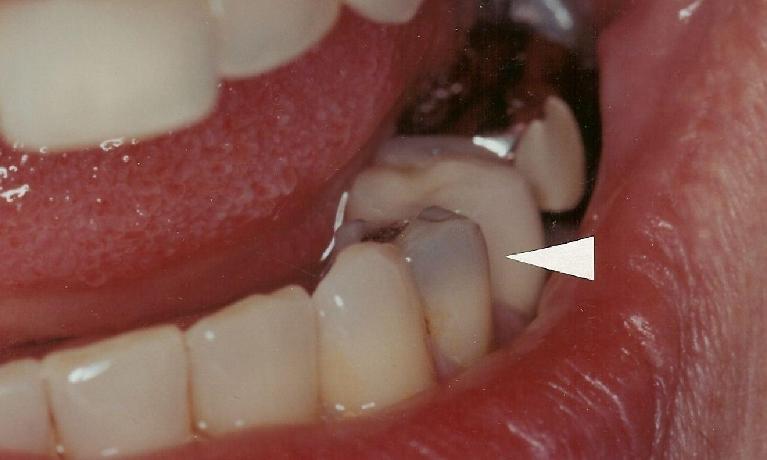

Ceramic Crown

This crown was replaced with an all ceramic crown. The gray discoloration has been eliminated.